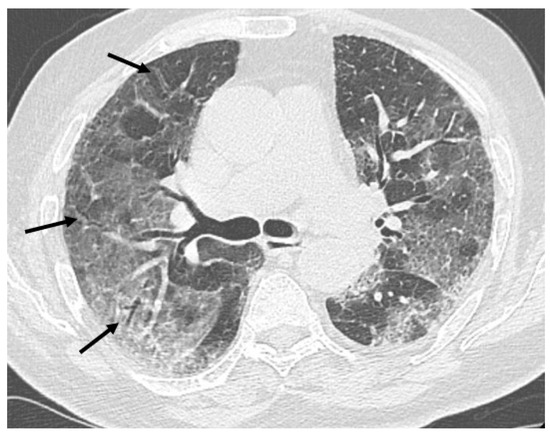

HRCT of the chest showed diffuse bilateral ground glass opacities (GGO) in all patients (Figure 1). Reticulation (Figure 2), traction bronchiectasis/bronchiolectasis (Figure 3), crazy paving and distortion (Figure 4) were observed in 29 patients (64%) at baseline. The total severity score was significantly higher at baseline in patients who eventually developed severe versus non-severe ARDS and pneumomediastinum/pneumothorax (16 versus 14; 95% CI 0.42 to 3.88; p = 0.01), as reported in Table 1. No other significant difference was observed at baseline.

Figure 3.

Bronchiolectasis (arrows) in the right lung.